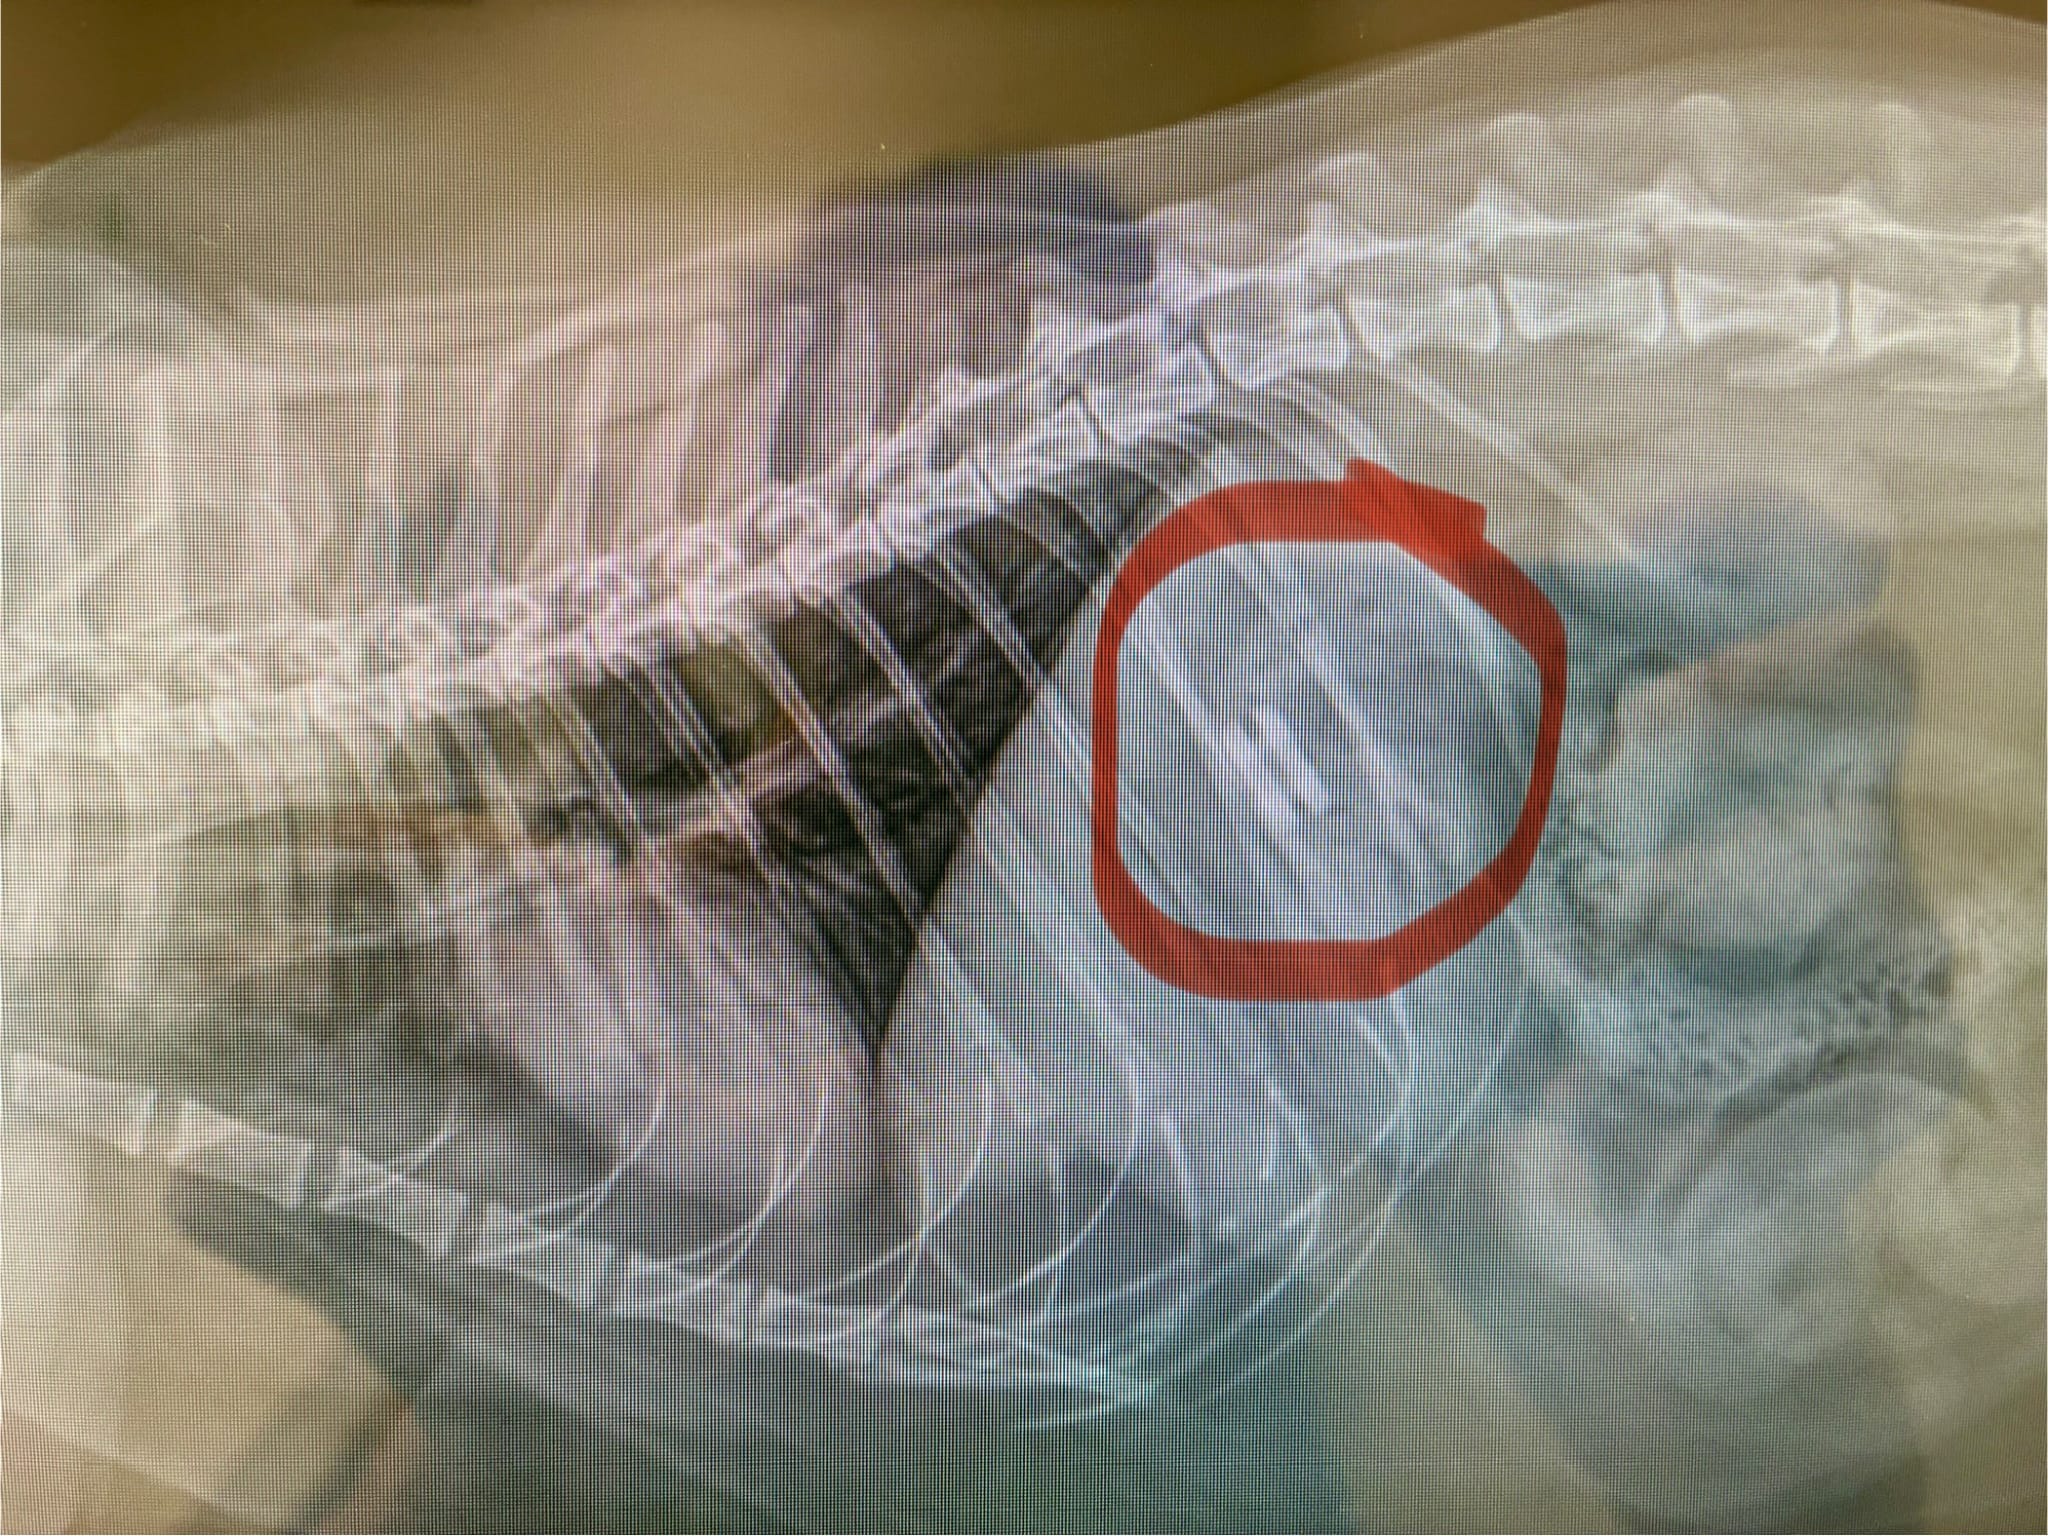

Enfoiré hasn't been feeling well for the past week. Yann took him to the vet for bloodwork, which already set Yann back $1k. The bloodwork came back normal, so Enfoiré was sedated so that he could be xrayed and get his mouth inspected.

The x-ray shows that Enfoiré has a foreign object stuck in his stomach. Not removing it has the potential to escalate things if the object moves lower in his intestine.